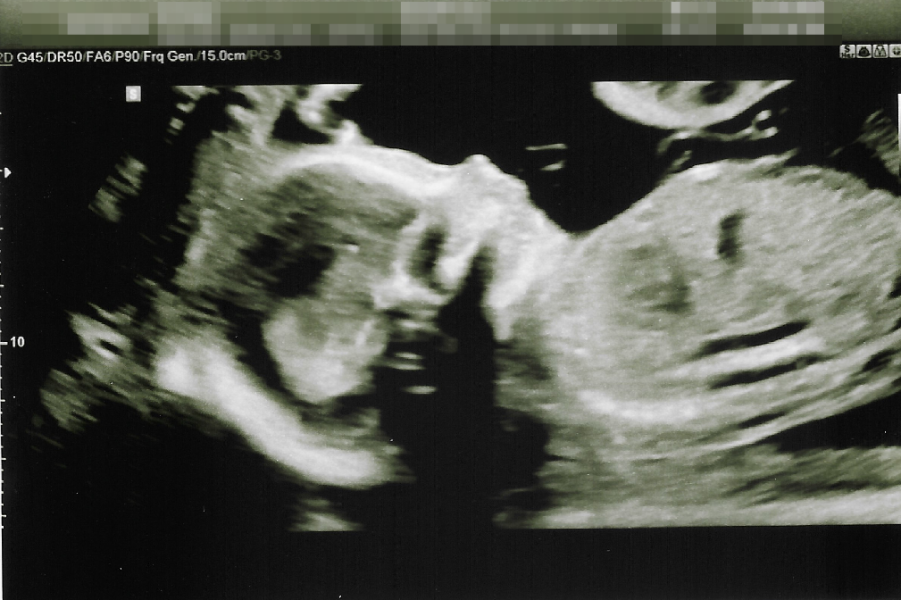

UPDATE: I had my 20 week scan this gone Monday (27th of October) and I'm having a gorgeous little baby boy! 💙😊

Forgot pic 😄